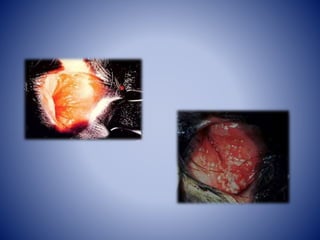

• Vulvovaginitis pustular infecciosa (IPV) es una

inflamación pustular causando enrojecimiento y

edema de la mucosa genital con vesículas y

pústulas evolucionando a úlceras.

La lesión primaria consiste en una necrosis focal de

las membranas mucosas genitales. Esta lesión es,

probablemente, la secuela directa de la replicación

del virus.